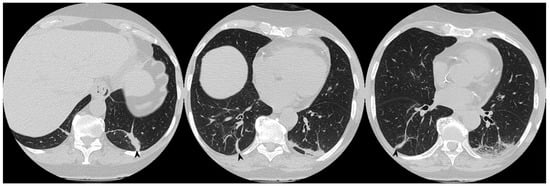

Figure 9. Migratory infiltrates. On the left (a): baseline HRCT; subpleural consolidation in the right lower lobe (white arrowhead). On the right (b): HRCT after 13 months of steroid therapy; the consolidations have disappeared in the first site, appearing in the left lower lobe (arrowhead).

In 14 of the 18 patients who presented consolidations at the first CT scan, a complete resolution of these consolidations was observed (Figure 8); however, in three of them, new ones showed up in different pulmonary areas (migratory infiltrates) (Figure 9). In the other four patients with consolidations on initial CT images, two patients had a partial resolution, whereas the remaining two cases have shown no differences in consolidations at follow-up HRCT. The changing consolidations are summarized in Table 5.

Figure 10. On the left (a): baseline HRCT; left parenchymal consolidations with air bronchogram sign in the context (arrowheads). On the right (b): HRCT after steroid treatment; new ground-glass areas (arrowheads) have appeared in the site of consolidations.

3.3. Ground Glass

Ground-glass opacities completely disappeared in nine out of 15 patients that have shown this pattern at baseline HRCT. In two patients, new ground-glass areas appeared where a previous consolidation was present, like residual components of the consolidations (Figure 10) (Table 6).